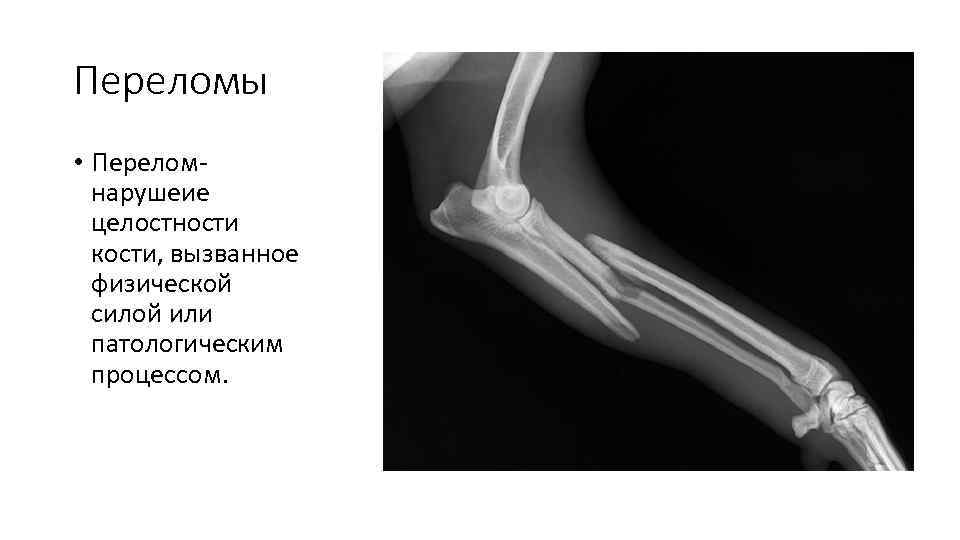

Переломы • Перелом- нарушеие целостности кости, вызванное физической силой или патологическим процессом.

клиника • резкая боль, усиливающаяся при любом движении • нарушение ее функции • отек в месте перелома • укорочение конечности • патологическая (ненормальная) подвижность кости • При пальпации области перелома — резкая боль, нередко костная крепитация • При открытом переломе в ране видны отломки костей, могут выступать